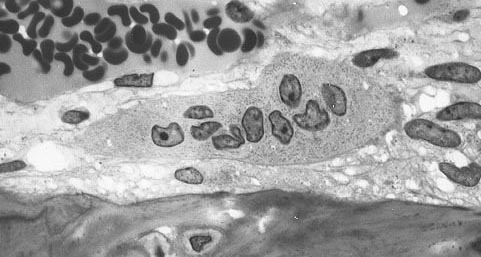

Osteoclast

Source: Osteoclast Date: 17 Oktober 2006 Author: Robert M. Hunt Licence: Public domain